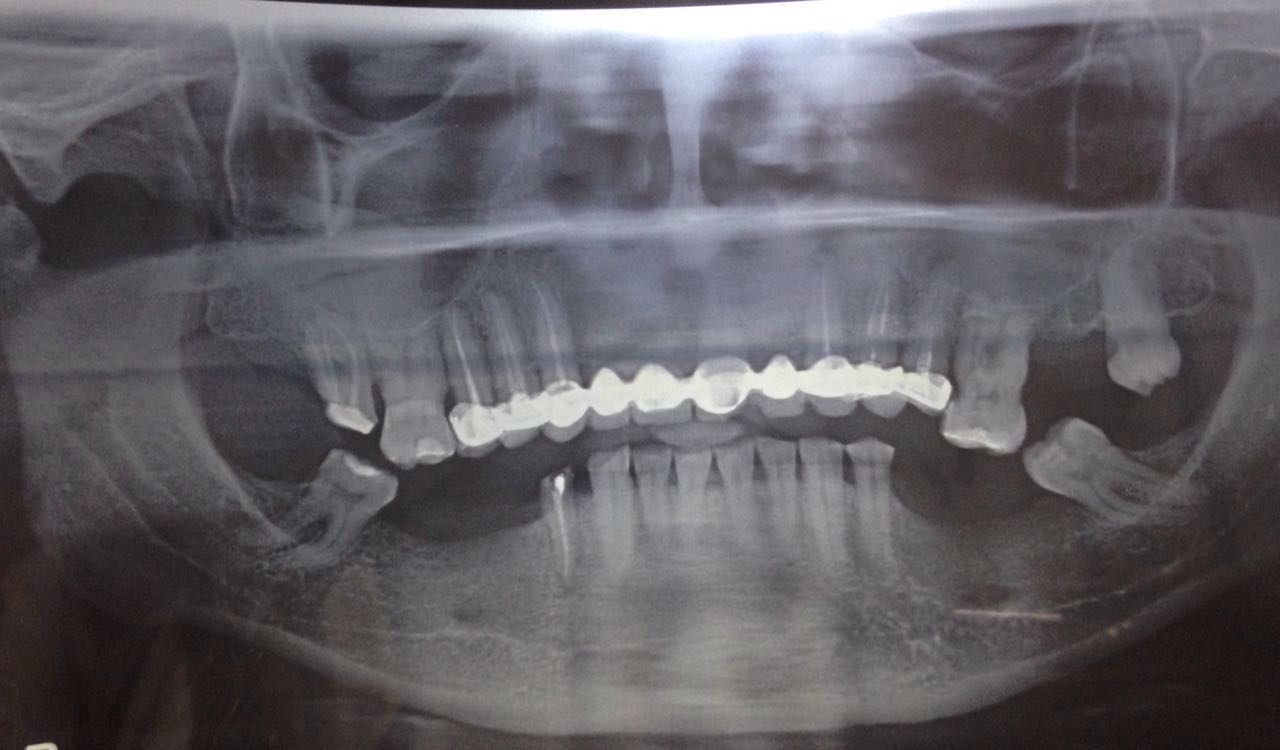

Full Mouth Case

Featured Case Studies